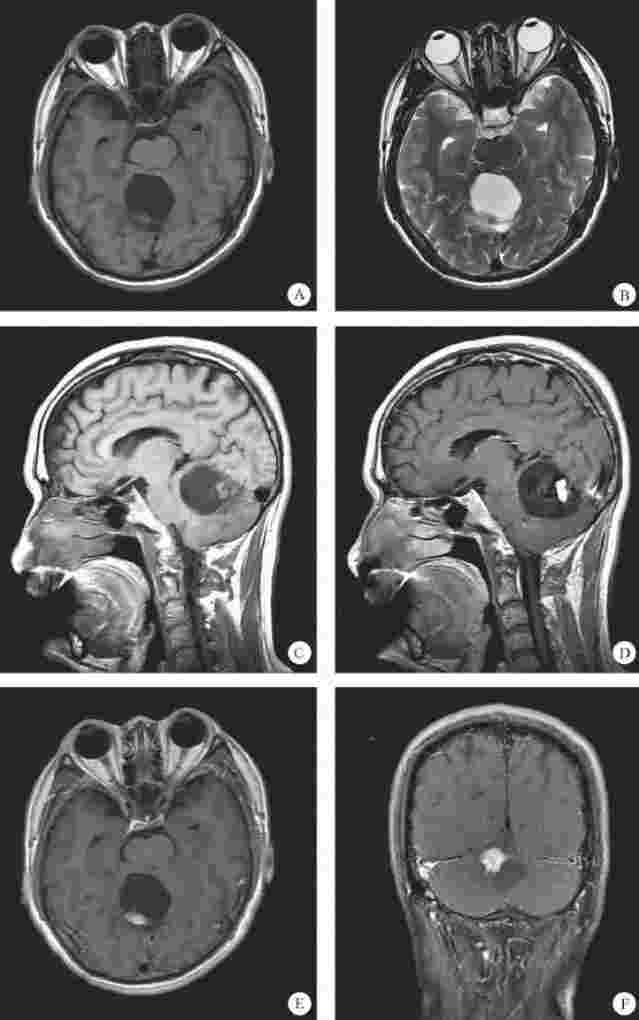

图3-23A、B、C,横断面T1WI、T2WI及矢状面T1WI示小脑蚓部囊性占位伴有壁结节,囊性部分呈长T1长T2信号,壁结节位于后部,呈稍短T1稍短T2信号,邻近壁结节可见流空的血管影。图3-23D、E、F,增强扫描壁结节呈明显强化。

图3-23 血管母细胞瘤MRI检查